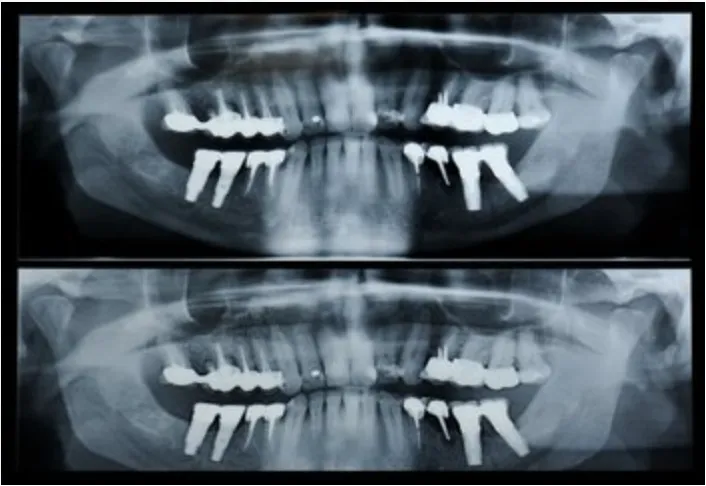

panorex dental x-ray images, Brookline, MA dentist

A panorex is a very impressive piece of imaging machinery in that it is capable of identifying many issues and structures that a normal x-ray is not. Initially you will sit in a chair with your chin on a small ledge. Once positioned in the machine, it will rotate around your entire head taking a full 360 degree view of the teeth, head, sinuses and bones.

The ability to view the full structure of your head as a whole is very informative to the dentist. It will allow us to see any potential problems and make sure that everything is functioning as it should be. The panorex is capable of viewing specific types of structural problems, infections or asymmetry among many others.